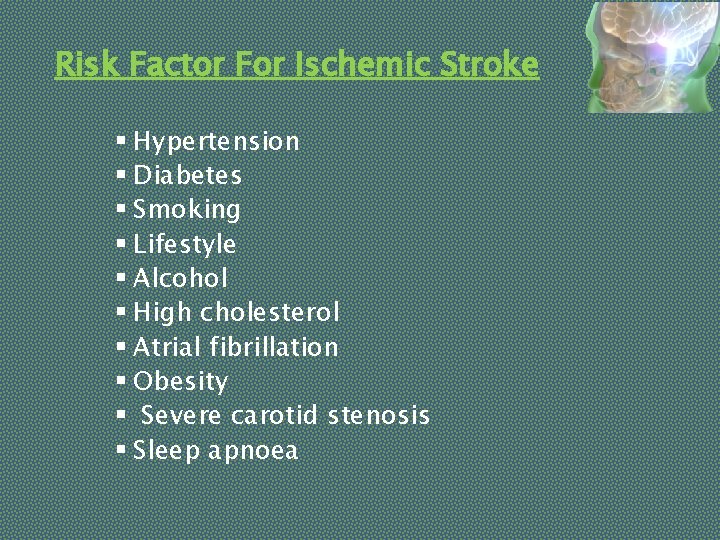

Risk Factor For Ischemic Stroke § Hypertension § Diabetes § Smoking § Lifestyle § Alcohol § High cholesterol § Atrial fibrillation § Obesity § Severe carotid stenosis § Sleep apnoea